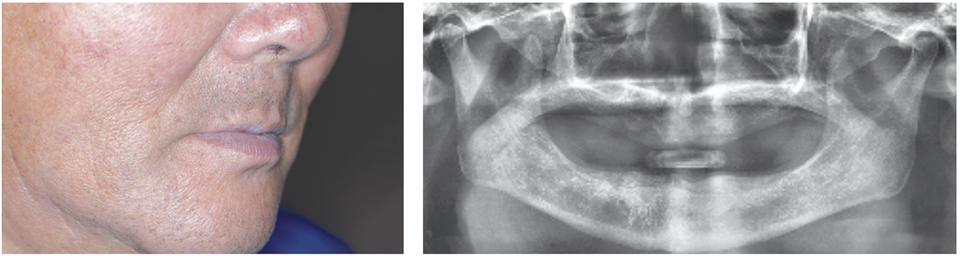

2) 안모와 방사선 검사

상악 치조제는 무치악 상태가 오래되어 치조골흡수가 많다.

하악 치조정은 수평적 치조골흡수가 많다.

악제 크기가 작고 치조골흡수가 많이 진행되었다.특히 후방 구치부 부위에 잔존치조제 크기가 너무 빈약하다.

(2)하악

틀니 유지에 필수적인 치조제와 retromolar pad가 빈약하다.